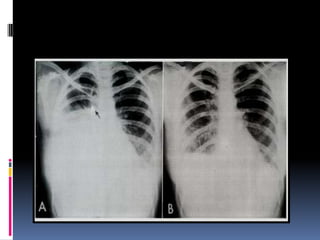

Penetration / Exposure

 Able to see ribs

through the heart

 Barely see the

spine through the

heart

Positioning / Rotation

Does the thoracic spine align in the center of the

sternum and between the clavicles?

Clavicles – equidistant from spine

Positioning / Rotation Doesthe thoracic spine align in the center of the sternum and between the clavicles? Clavicles – equidistant from spine

Determine side –? L/R  Gastric bubble should be on the left ( normally )